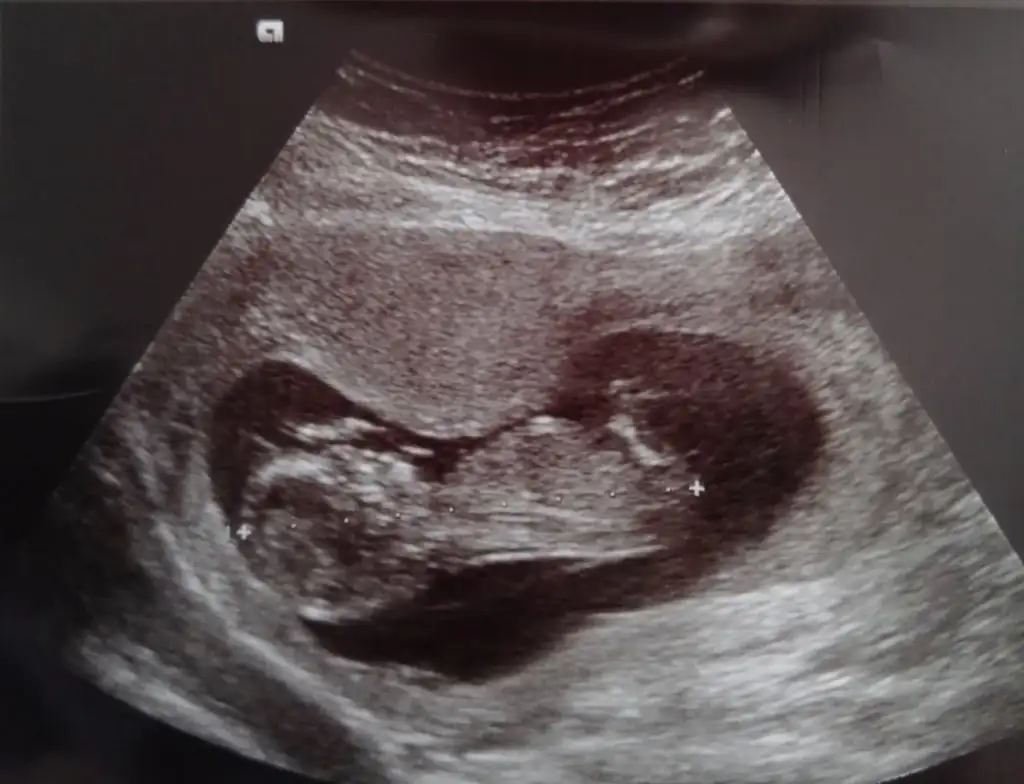

Çok üzüldüm arkadaşımıza rabbim sabır versin.benim de gunlerim mide bulantısı ve korkuyla geçiyor.tek yumurta ikizi oldukları için riskli.rabbim sağ salim kucağımiza almayı nasip etsin